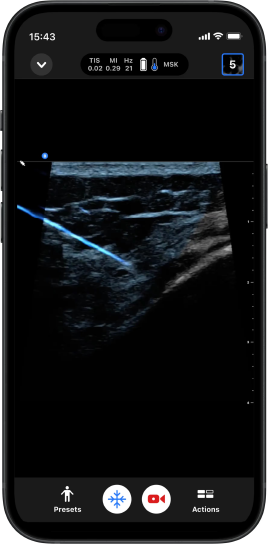

NeedleViz™

Isso facilita a identificação da agulha e a obtenção do controle necessário durante procedimentos guiados no plano.